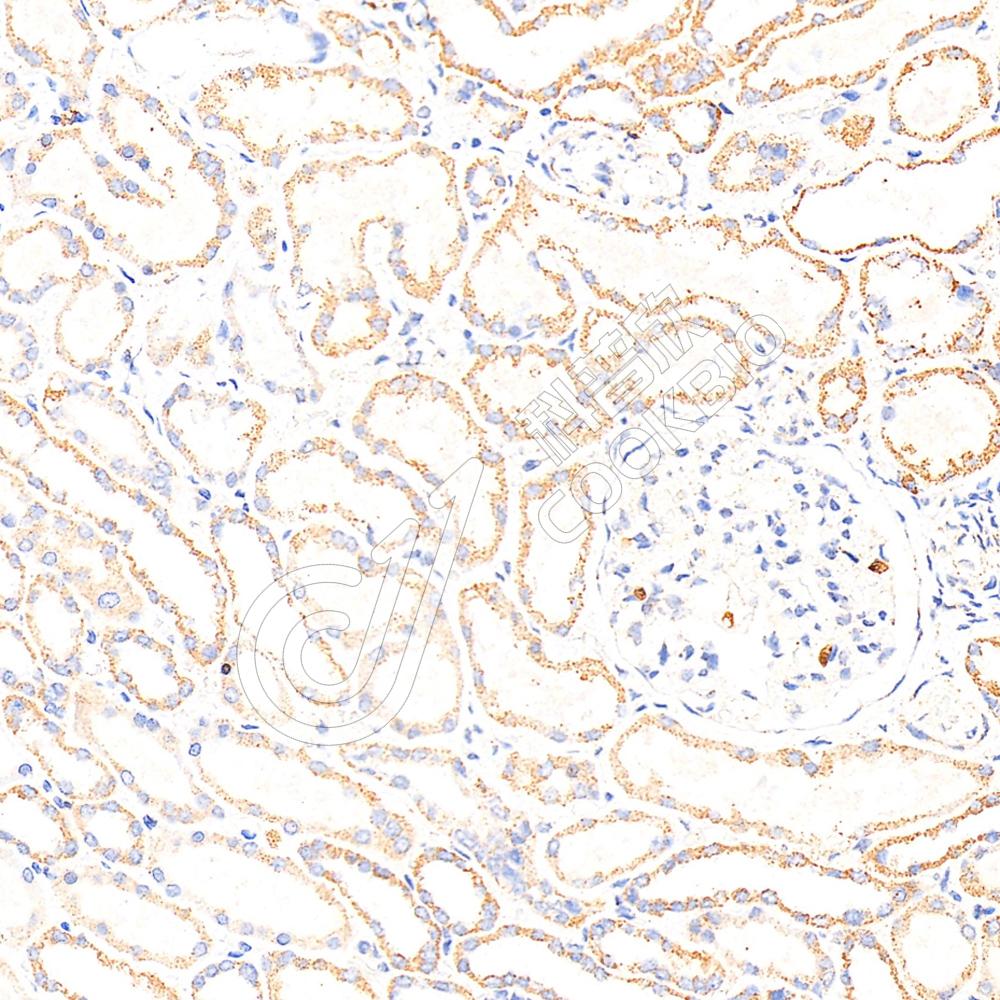

IHC检测Skp1蛋白(货号 K1333690).

样品: 人卵巢癌, 4%多聚甲醛 (货号KSG1101) 固定12-24小时.

抗原修复: 柠檬酸抗原修复液(干粉, pH 6.0) (KSG1201), 98℃, 20分钟.

—抗: 1: 2300稀释, 4℃ 孵育过夜.

二抗: S-vision免疫组化多聚二抗(山羊抗兔),即用型 (货号KB3906), 室温孵育20分钟.